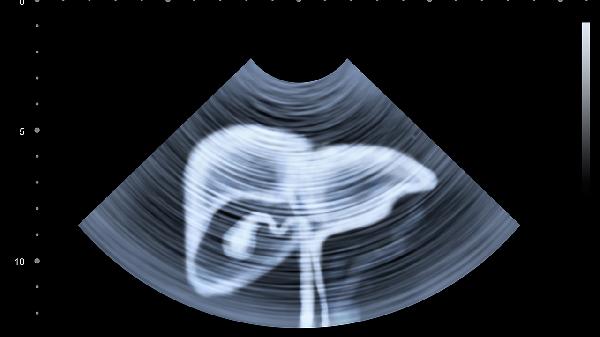

偶尔肝脏刺痛怎么办?

偶尔考虑肝痛是由肝炎或肝硬化引起的,患者需要在医生的指导下使用药物来缓解。

1、肝炎:

肝炎通常是由病毒感染、高能量饮食等原因引起的。患者患病后会出现恶心、食欲不振等症状。有些患者偶尔会出现肝脏刺痛。患者可以在医生的指导下使用药物。常见的药物有利于巴韦林胶囊、拉米夫定片等。

2、肝硬化:

肝硬化是由大量饮酒、寄生虫感染等原因引起的。患者患病后会出现腹部不适、乏力等症状,有的患者偶尔会出现肝脏刺痛的症状。患者需要在医生的指导下用药。常见的药物有螺内酯片、呋塞米片等。